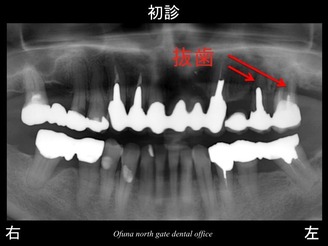

上顎左側の奥歯に問題がありました。

歯肉が腫れ、グラグラとしてきたため、当医院を受診されました。

まず、第一に 神経がないことです。

次に ブリッジ形態になっていることです。

次に上顎左側の奥歯がブリッジになっていることです。

上記の2つが大きな原因ですが、他にも歯根破折した原因があります。

それが 骨吸収です。

いつものように 骨吸収の状態を分かりやすくするために

骨吸収の状態を線で書いたのが以下のレントゲンになります。

青線が骨吸収を起こす前の骨の位置です。

赤線は、現在の骨の位置です。